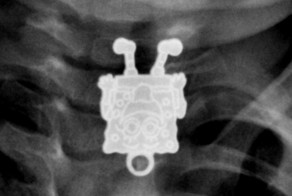

Маленькая Брук Гринберг (Brooke Greenberg) плохо говорит, сидит в коляске и у нее до сих пор молочные зубы. Несмотря на то, что она выглядит как ребенок, девочка родилась в 1993 году и ей уже 20 лет.